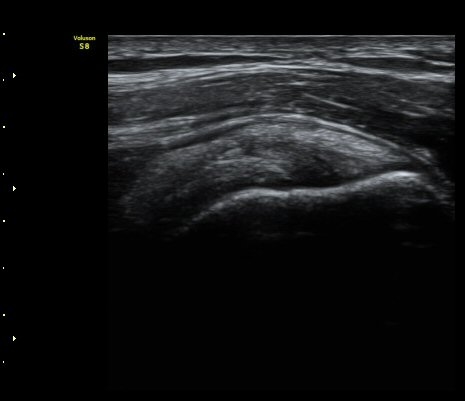

±Ø»ó°ÇÀÇ È¾´Ü¸é°Ë»ç¿Í Á¾´Ü¸é°Ë»ç¿¡¼­ ±Ø»ó°Ç³»¿¡ °í¿¡°í ¼®È¸È­ À½¿µÀÌ

°üÂûµÈ´Ü(»çÁø 1, 2).